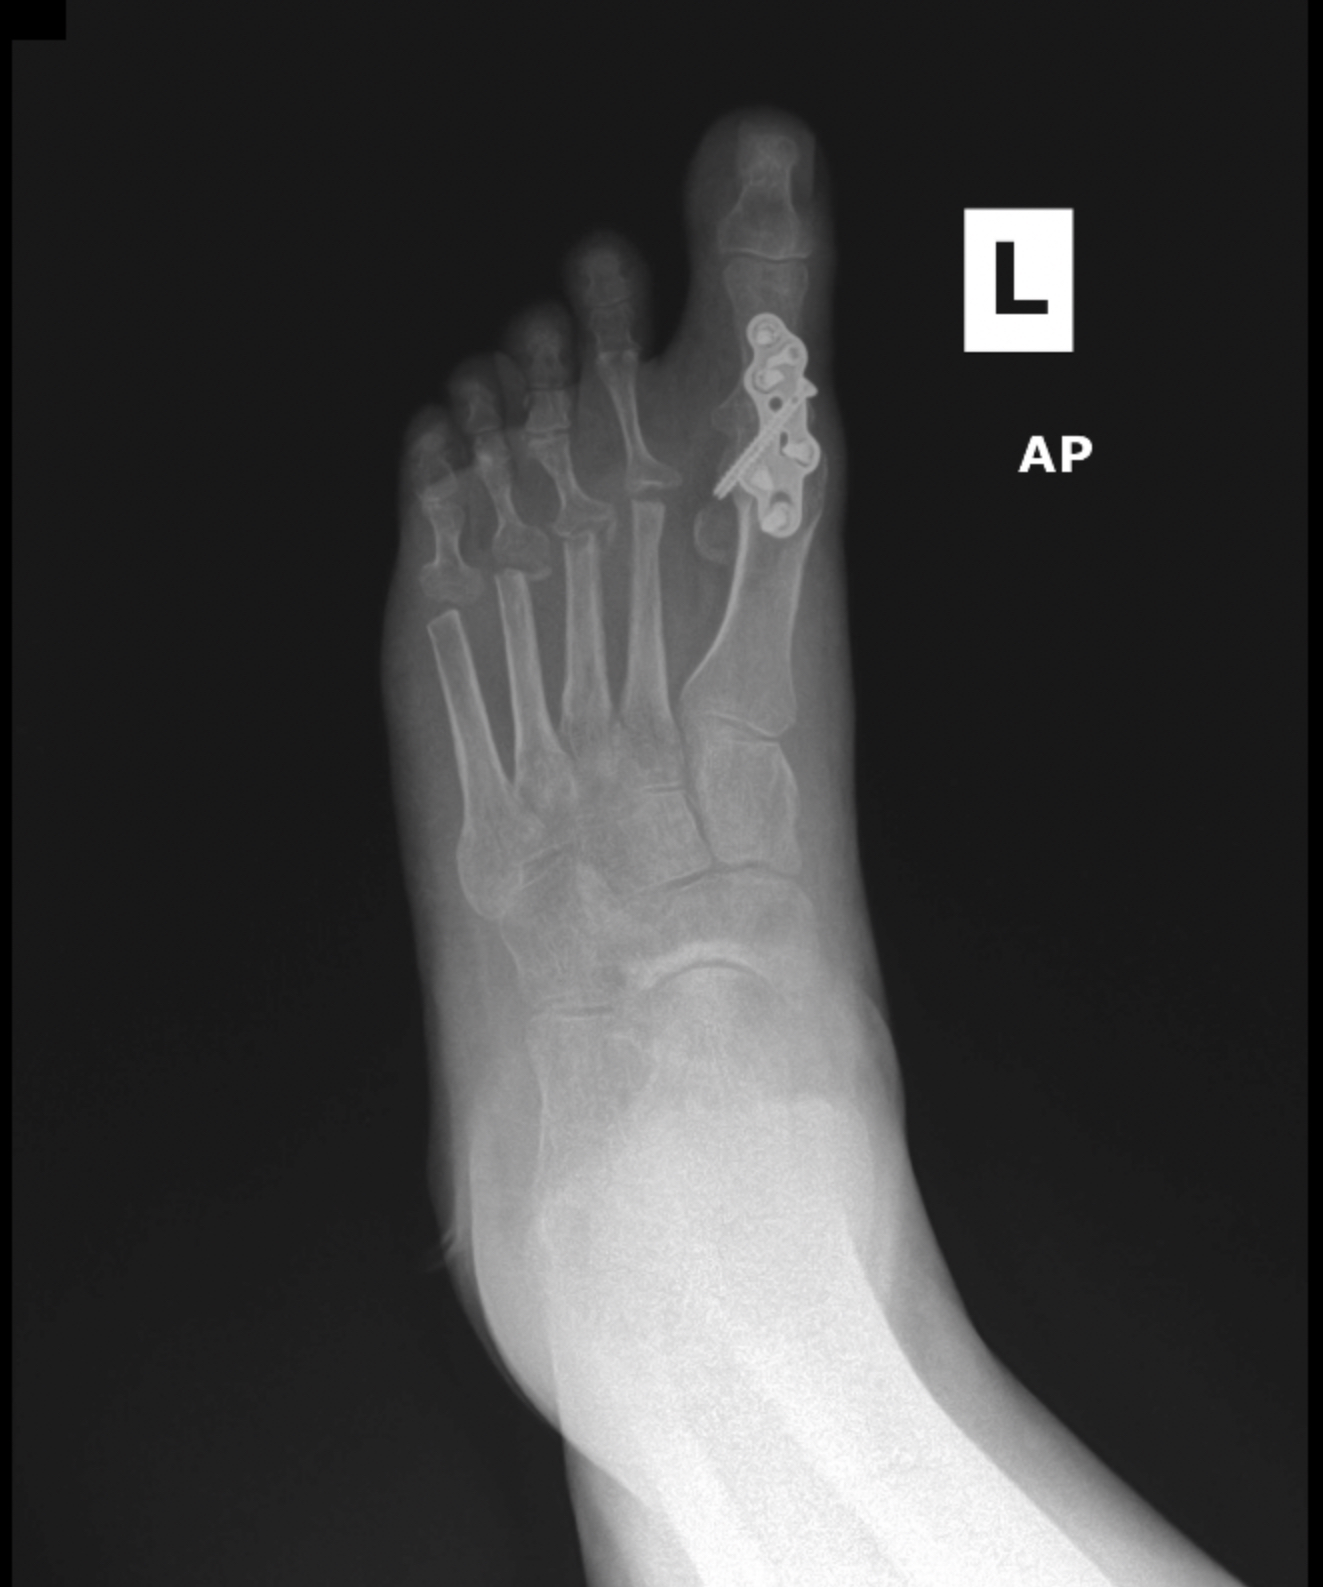

MIS Bunion

MIS3

MIS2